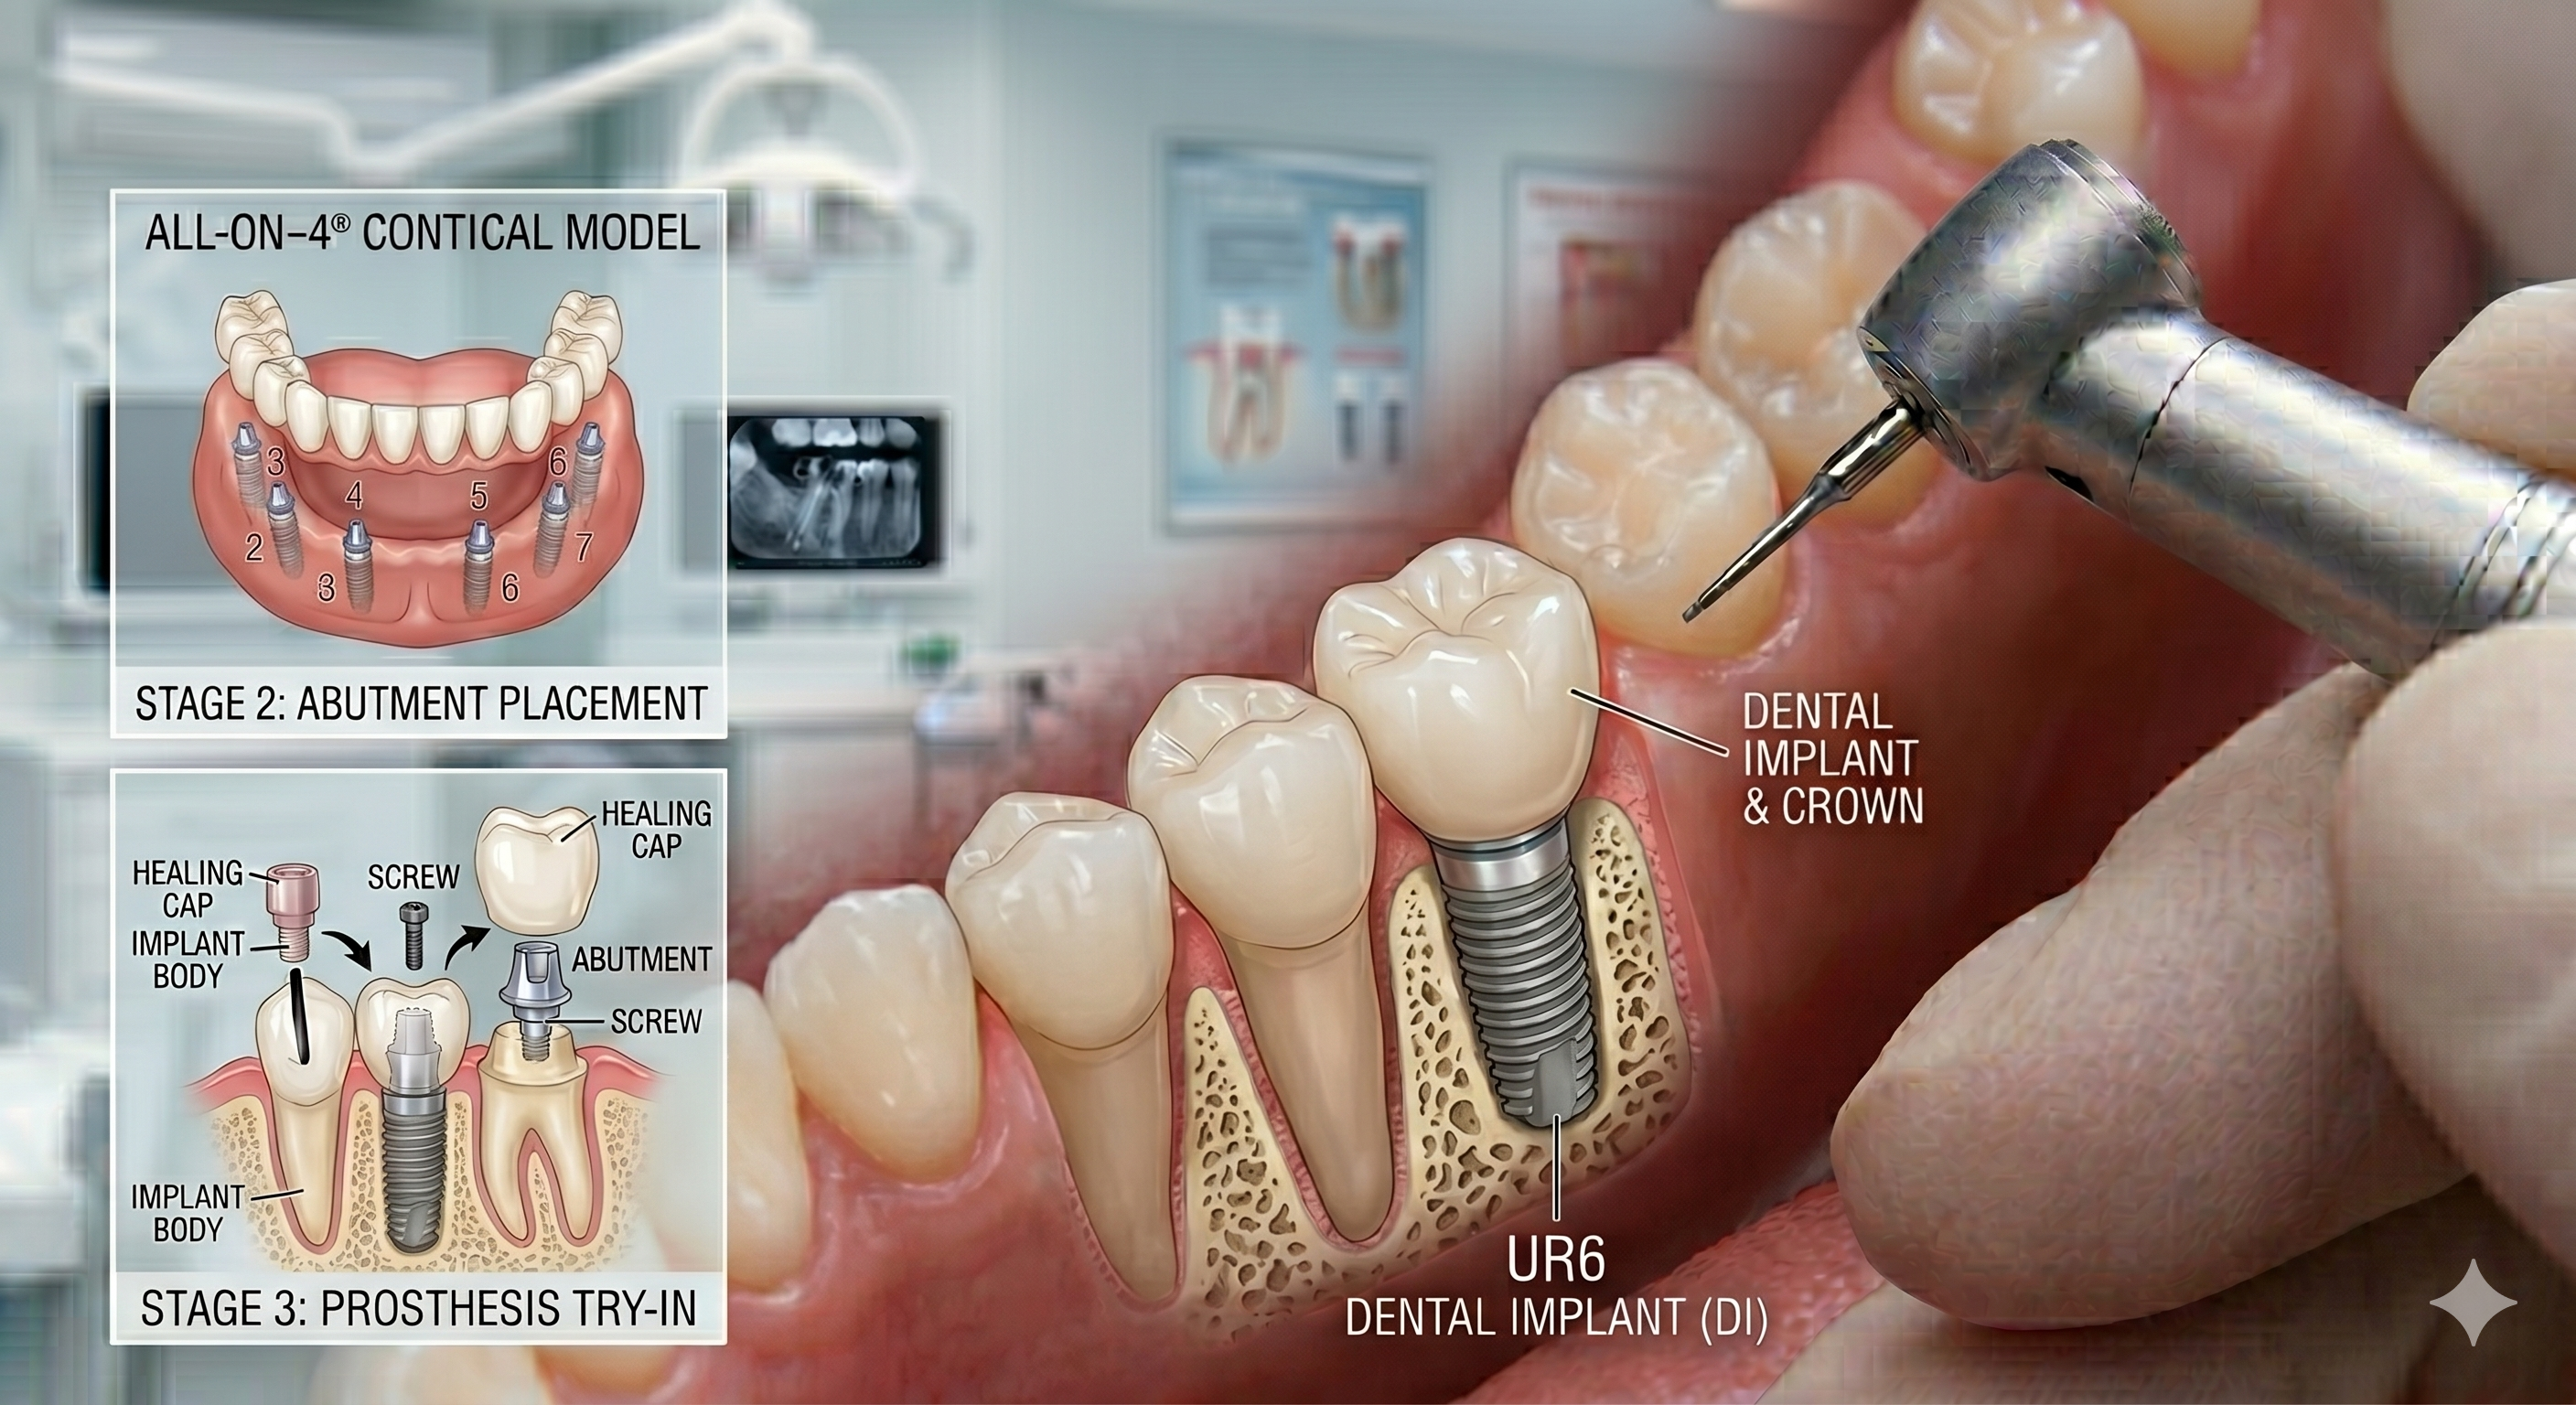

Dental Implant

The gold standard for tooth replacement. Our dental implants provide a permanent, stable foundation for crowns that look, feel, and function exactly like natural teeth. It is a long-term solution that also helps preserve your jawbone health.